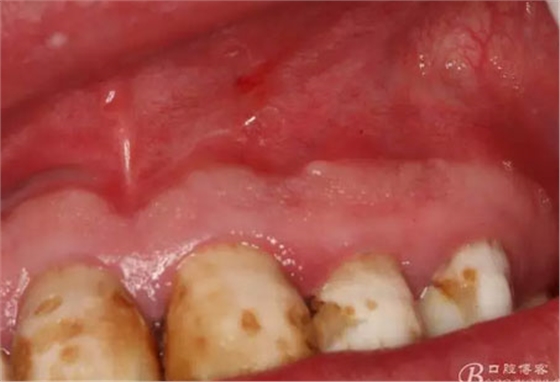

圖4.囊腫術(shù)前的口內(nèi)檢查:21、22牙冠未變色、唇側(cè)粘膜色澤正常,無瘺管,可在前庭溝捫及隆起,有乒乓感。